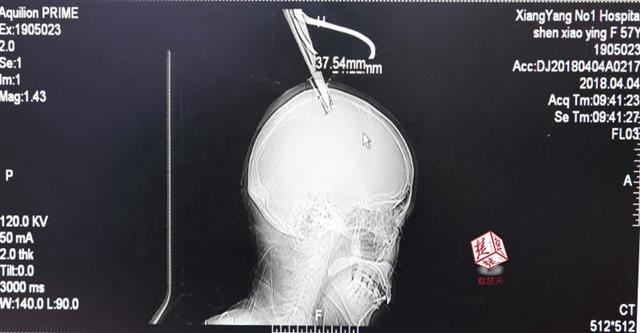

4月4日清晨,襄陽市樊城區(qū)太平店鎮(zhèn)57歲的農(nóng)村婦女沈某,在采摘香椿嫩芽時,綁在竹桿上的剪刀因竹子腐朽不慎折斷,剪刀斜插入頭顱。經(jīng)過及時搶救,目前脫離生命危險。

醫(yī)生檢查發(fā)現(xiàn),剪刀刀尖斜嵌在沈某顱骨里,離腦髓只有兩三毫米。所幸是斜著插進去,如果是垂直刺入,很有可能造成癱瘓。最終經(jīng)過手術(shù),剪刀被取出,沈某目前仍在ICU進一步觀察。